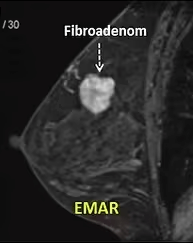

Meme Fibroadenomları

Fibroadenomlar kadınların yaklaşık %10 unda rastlanan memenin iyi huylu tümörleridir. Genç kadınlarda, özellikle 15-30 yaş arasında daha sık görülürler. Östrojen etkisiyle büyüdüklerinden üreme çağında ve hamileliklerde büyüme hızlanır. Fibroadenomlar muayenede elin altından kayan, hareketli ve lastik kıvamında kitleler şeklinde hissedilirler. Tek ya da çok sayıda olabilirler, çapları genellikle 3 cm nin altındadır ancak bazen dev boyutlara ulaşabilen fibroadenomlar da görülebilir.

Fibroadenomlar ultrason, mamografi ve emar’da kolayca görülebilirler.